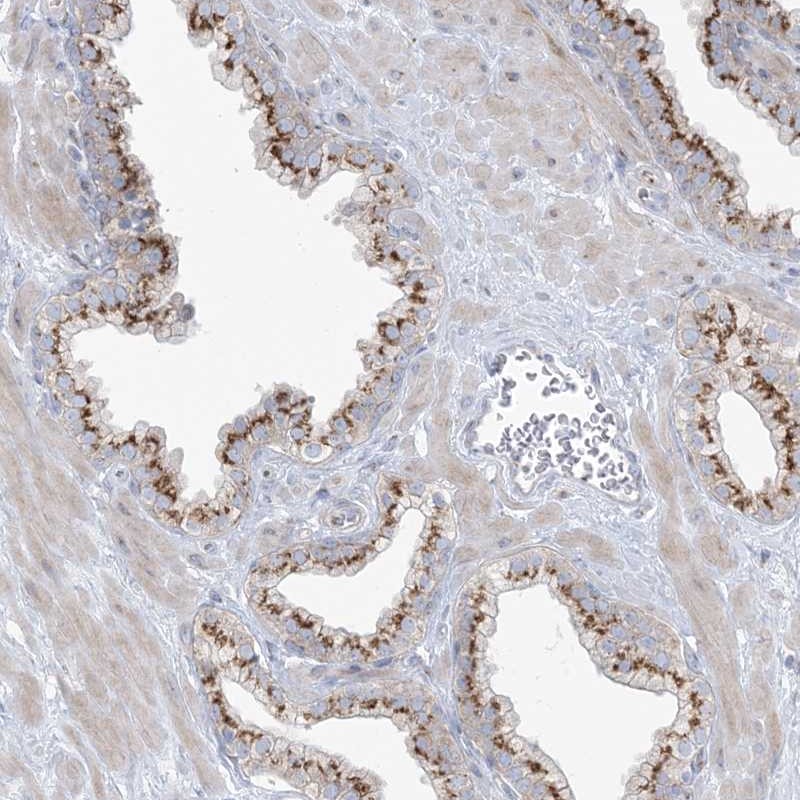

Immunohistochemical staining of human prostate shows strong cytoplasmic positivity in glandular cells.